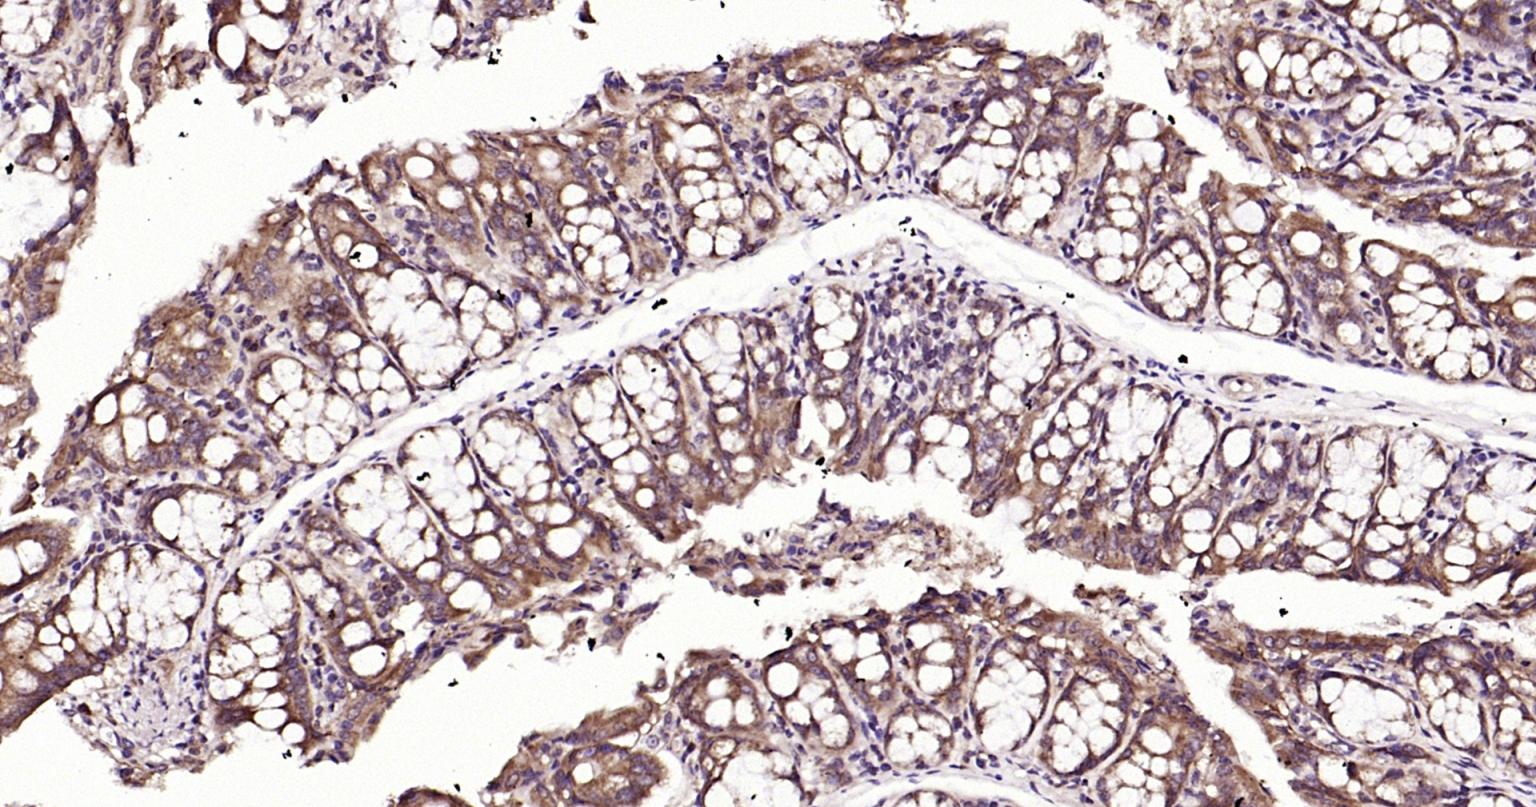

| IHC-P | Human, Mouse, Rat | Rabbit | 1:400-800 |